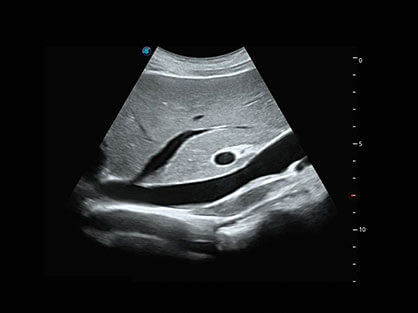

作为P系列家族成员之一,P40 Plus采用玖鼎集团高端超声系统平台——极光,并以时尚秀丽、小巧灵动的外观设计绽放出灵动之韵、科技之美。高端平台的使用保证了P40 Plus优质的基础图像;完备的高级功能可满足您全身应用的基本需求;丰富的探头配置、多样的高级4D成像及分析软件为您日益增多的妇产应用需求提供丰富的诊疗方案。

结合玖鼎集团超宽频带探头技术优势,能够更好地获得高分辨力与高穿透力的平衡,保证图像质量,为临床诊断保驾护航。

微米成像技术提升了对组织斑点噪声信号的抑制能力,并进一步强化边界信息,从而获得清晰图像。